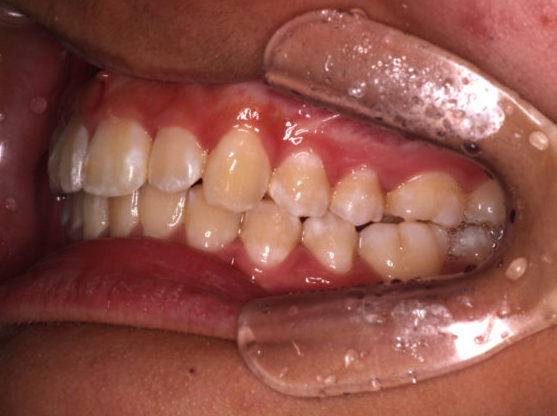

初診時の写真です。

前歯にはがたつき(叢生)がみられ、奥歯は上の歯と下の歯が1歯対1歯で噛んでいることがわかります。

つまり出っ歯の噛み合わせです。

診断:上顎前突・前歯部叢生